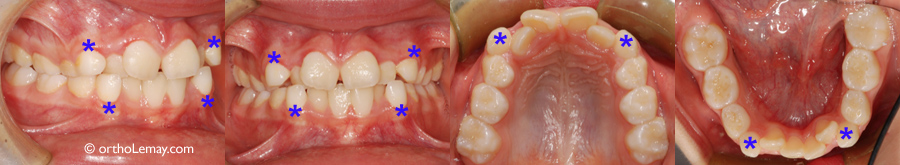

Chevauchement important aux 2 arcades chez une jeune fille de 9 ans. Des extractions sélectives (canines temporaires indiquées par des astérisques *) permettront de désencombrer les dents antérieures et d’aider les problèmes d’éruption qui affecteront les autres dents permanentes.